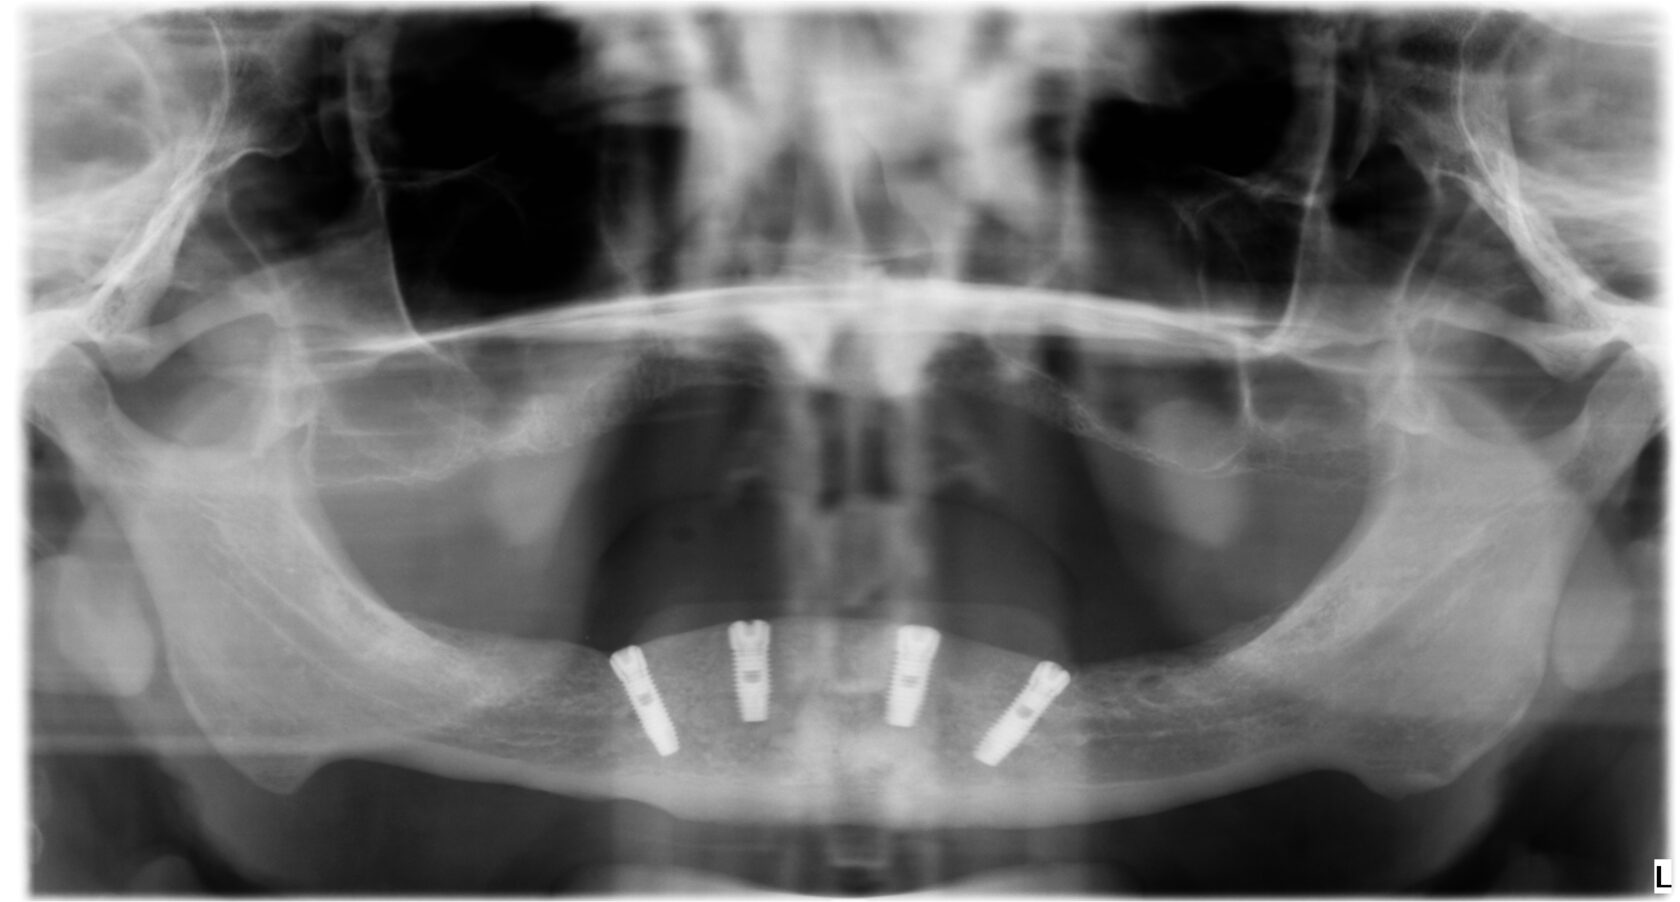

All-on-4

Эта методика подразумевает использование четырех имплантатов для поддержки несъемного протеза. Имплантаты размещаются под углом в задней части челюсти, что позволяет использовать максимальную длину костной ткани без необходимости в дополнительной костной пластике. Это также дает возможность использовать более короткие имплантаты в местах с ограниченной высотой кости.